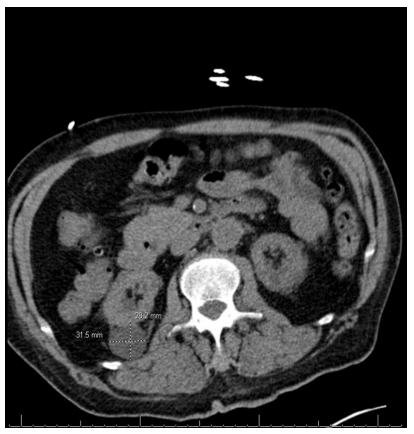

CT abd/pelvis (Figure 2) showed b/l common iliac artery aneurysms(right 2.8cm, left 2.6cm), atrophic kidneys with b/l renal cysts, and a trace right pleural effusion.

Figure 2 : CT abdomen/pelvis showing a right iliac artery aneurysm that measures 3.1cm x 2.8cm